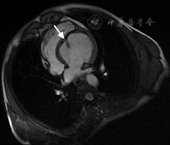

入院后生化检查:总胆固醇3.4 mmol/L,低密度脂蛋白胆固醇1.9 mmol/L;甲状腺功能三项无异常;空腹血糖4.4 mmol/L;急查心肌酶无异常,肌钙蛋白I阴性;血尿常规、肝功能、肾功能和凝血功能正常。器械检查:(1)X线胸片:心影不大,呈球形,心胸比例0.44。(2)12导联心电图(图1):窦性心律,电轴右偏,胸前导联R波递增不良,V1或V2导联正向T波高度大于V5或V6导联。(3)超声心动图(图2、图3):左心室增大,呈球形改变,左心室横径59 mm,纵径84 mm,前后径64 mm;左心室射血分数52%,短轴缩短率26%;左心室心尖部扁平,似被截短;左心室室间隔均凸向右心室,前间隔、后间隔中间段至心尖段心肌变薄(厚度4.8 mm),回声增强,运动消失;前间隔、后间隔基底段心肌厚度正常,运动减弱,呈瘤样凸向右心室,致右心室流出道局部梗阻(内径变窄,8.5 mm;流速偏快,1.95 m/s;右心室流出道压差20 mmHg);左心室乳头肌均附着于扁平的左心室前壁心尖部;舒张早期二尖瓣血流峰值速度(E)1.07 m/s、舒张晚期二尖瓣血流峰值速度(A)0.76 m/s,E/A=1.4;其余房室腔内径正常;右心室射血分数58%。(4)动态心电图:窦性心律,电轴右偏,胸前导联R波递增不良,Tv1(Tv2)>Tv5(Tv6);24 h最低心率54次/min,最高心率121次/min,平均心率72次/min;偶发房性早搏;无室性心律失常;心率变异性正常。(5)冠状动脉造影未见明显异常。(6)左心室造影:心腔扩大,左心室心尖部在舒张期呈球样扩张,且搏动减弱。(7)心脏磁共振(图4):左心室舒张期呈球形扩张,舒张末期前后径64 mm;室间隔向右心室面突出;心尖及心尖段室间隔左心室面可见脂肪替代且运动减低,中间段室间隔变薄(厚度5 mm);右心室心尖向左延伸,包绕发育不良的左心室心尖部;左心室前后两组乳头肌均附着于前壁心尖部。

LVAH有特殊的形态学改变,影像学诊断标准包括:(1)最突出特征是左心室心尖部扁平,乳头肌附着点以远似被截平;(2)室间隔凸向右心室侧,致使左心室横径增加,纵径相对缩短,失去其圆锥形外观而呈球形;(3)左心室乳头肌附着于其扁平的前壁心尖部,而非前侧壁和后中壁,此种改变可致不同程度的二尖瓣反流;(4)右心室形态学改变表现为远端延长,并包绕发育不良的左心室心尖部,呈香蕉状,功能多正常;(5)大部分患者左心室心尖部可见脂肪替代[2]。超声心动图是临床筛选LVAH的最常用方法,但易受操作者经验及声窗的影响。心脏磁共振是目前诊断LVAH的最好方法,有良好的软组织分辨率,本例患者最终经心脏磁共振确诊。